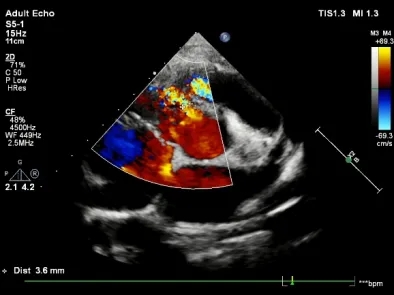

术前TTE示:膜周部室间隔缺损,基底大小11.3×10.5mm,分流口大小3.6mm,左向右分流,峰值流速4.07m/s。

术前TTE示:房间隔缺损继发孔型,断端大小4.5-5mm,薄弱范围约10mm,左向右分流 。

术前造影:室间隔缺损处造影,造影显示有膜部瘤形成,测量缺损大小,左侧基底大小10.8mm,右侧分流口2处,分流大小约2mm。

释放前超声下封堵器型态良好,骑跨室间隔两侧

释放后超声

超声下可见室水平和房水平都无残余分流

心脏彩超:心脏超声下可见两个封堵器双盘稳固夹持,无残余分流;

术后1个月心脏超声,房室水平皆无残余分流